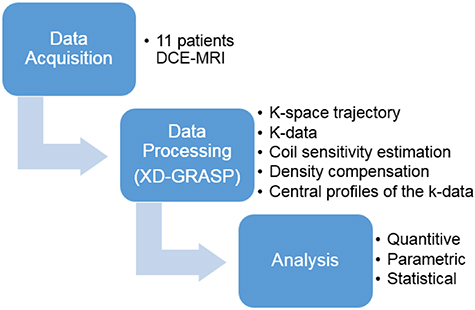

This study was based on free-breathing acquisitions from 11 patients which were reconstructed using the XD-GRASP technique with different number of motion states followed by several analyses (figure 1). This prospective study was approved by our institutional review board and consent was obtained from all patients. Eleven patients, 6 men and 5 women (70 years ±11 [standard deviation]) diagnosed with HCC, with tumors exceeding 10 mm, underwent DCE-MRI examinations between September 2018 and December 2018.

Figure 1. Overview of the study plan.